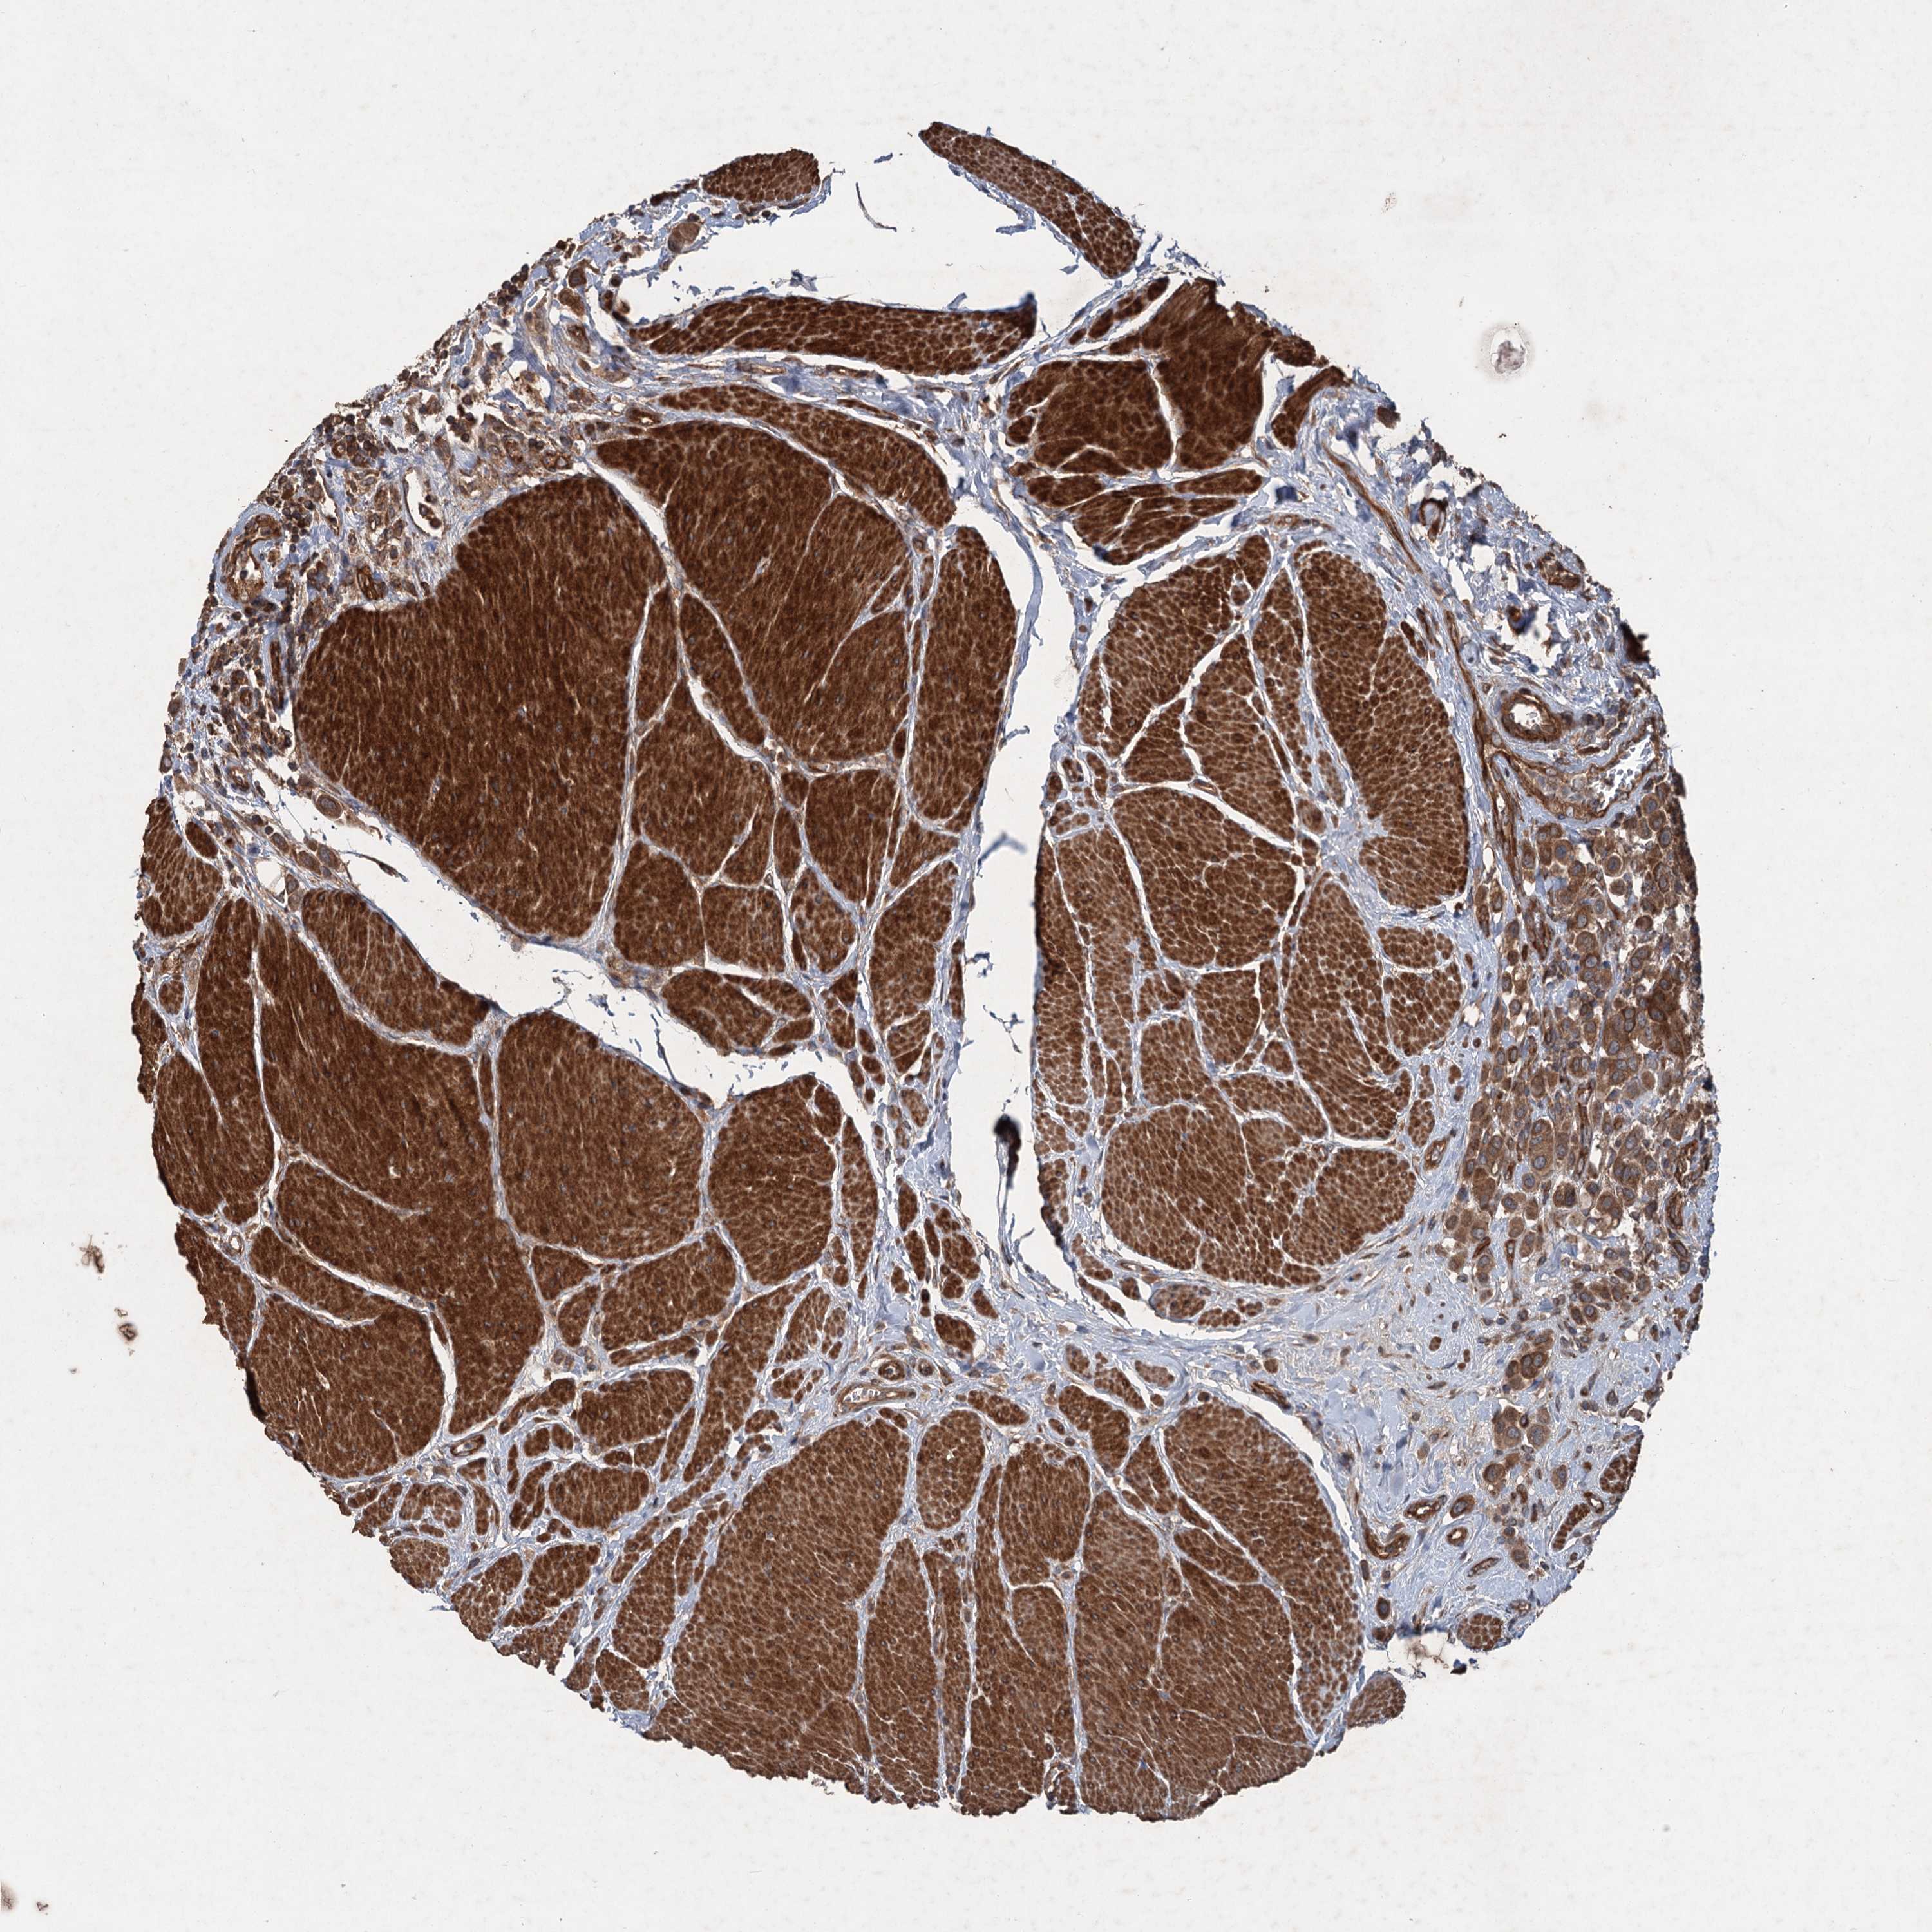

UROTHELIAL CANCER - Protein expressioni

A mouse-over function shows sample information and annotation data. Click on an image to view it in a full screen mode. Samples can be filtered based on level of antibody staining by selecting one or several of the following categories: high, medium, low and not detected. The assay and annotation is described here.

Note that samples used for immunohistochemistry by the Human Protein Atlas do not correspond to samples in the TCGA dataset.

Antibody stainingi

Antibody staining in the annotated cell types in the current human tissue is reported as not detected, low, medium, or high, based on conventional immunohistochemistry profiling in selected tissues. This score is based on the combination of the staining intensity and fraction of stained cells.

Each image is clickable and will lead to virtual microscopy that enables deeper exploration of all samples and also displays staining intensity scores, fraction scores and subcellular localization as well as patient and tissue information for each sample.

Antibody HPA039332

Staining

High

Medium

Low

Not detected

Intensity

Strong

Moderate

Weak

Negative

Quantity

>75%

75%-25%

<25%

None

Location

Urothelial carcinoma, High grade

Urothelial carcinoma, Low grade

Urothelial carcinoma, NOS